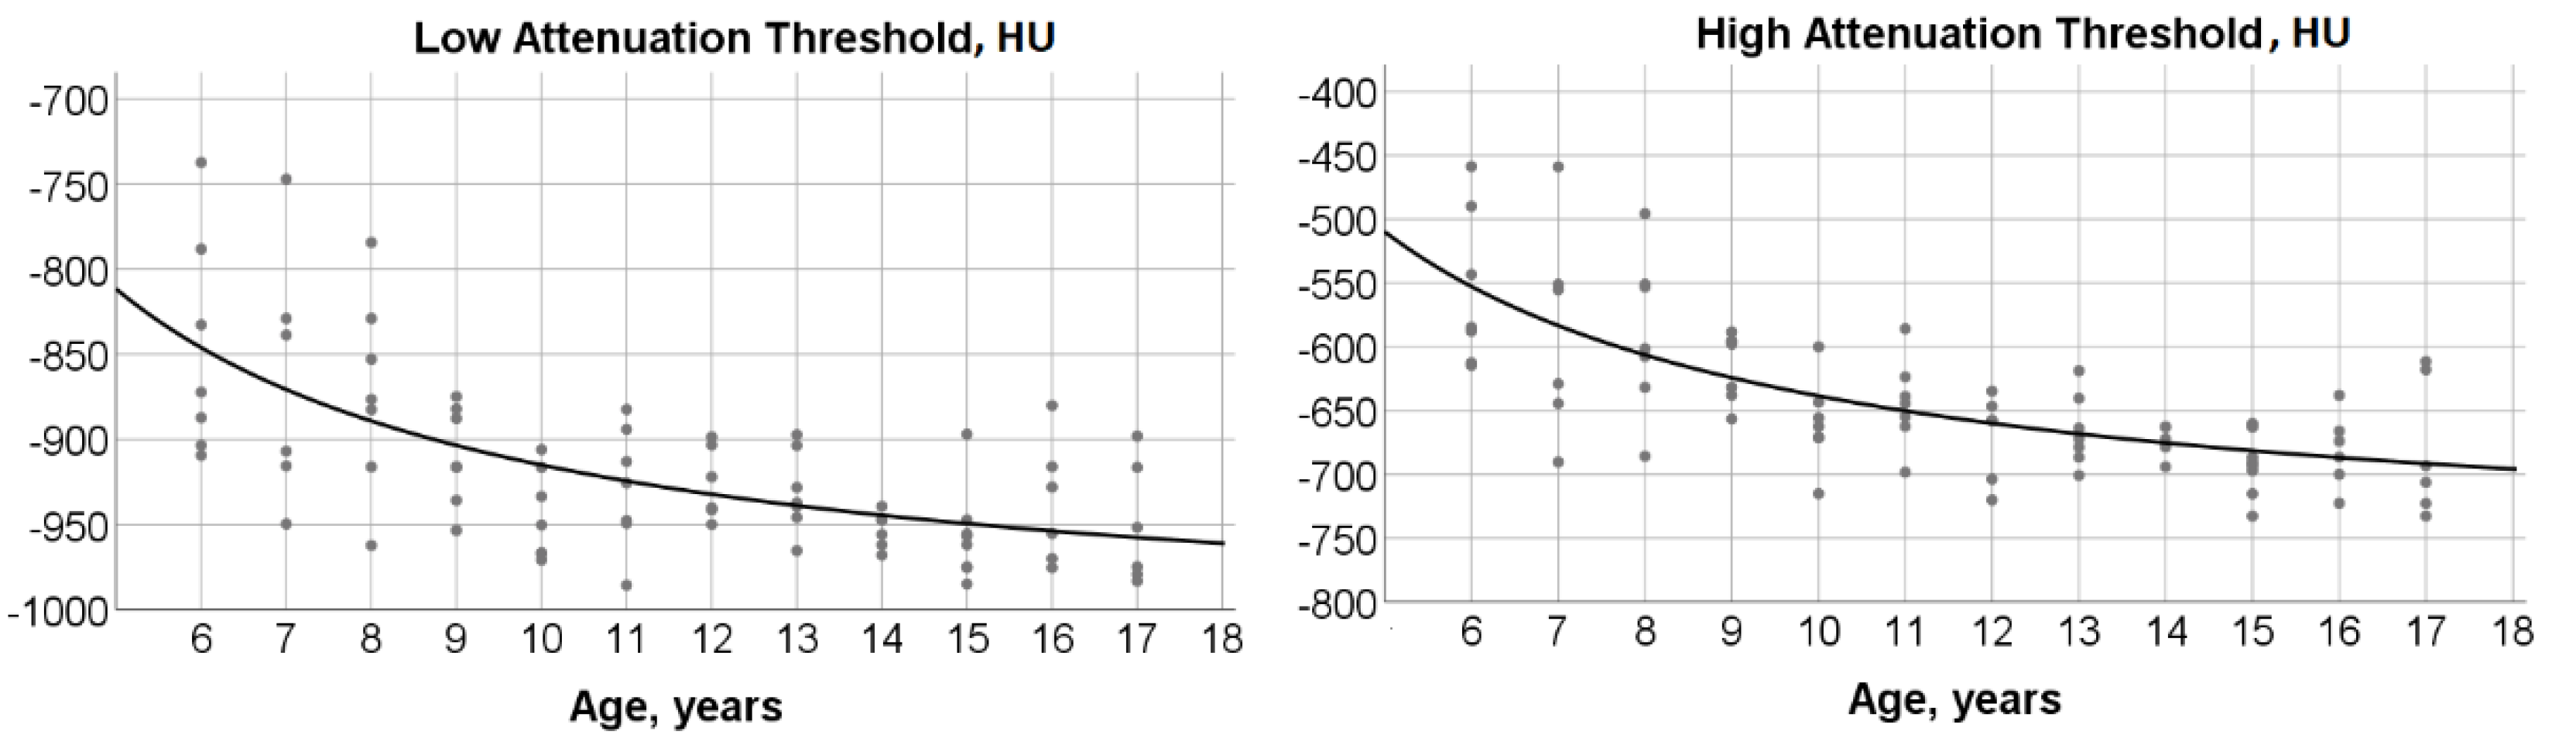

3.3. Age-Dependence of Low and High Attenuation Thresholds

3.4. %TLCCT with Low or High Attenuation and Their Associations with Age and TLCCT